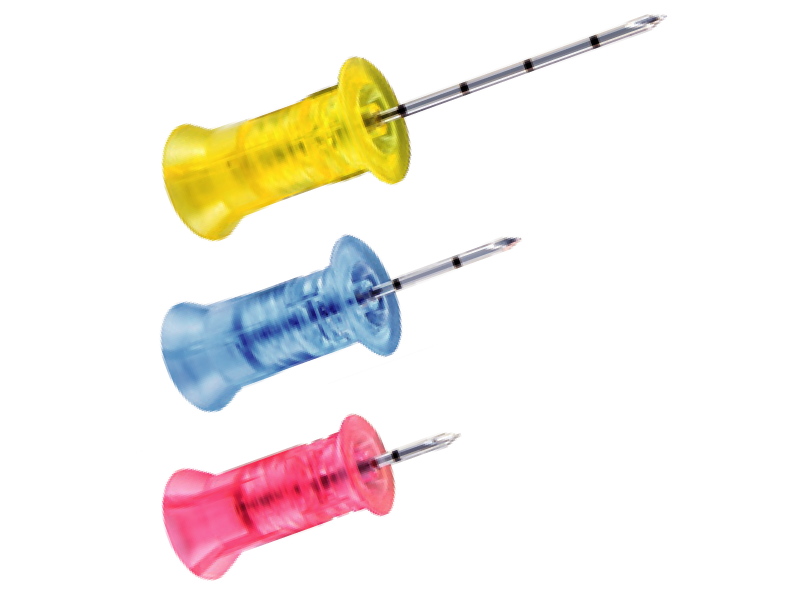

Needle set (with stabilizer) - 45 mm , 25 mm , 15 mm |